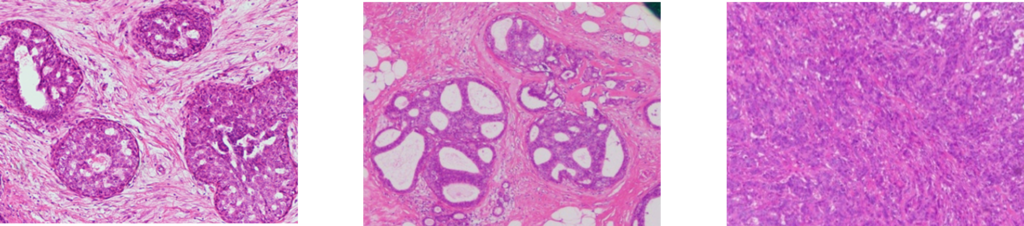

良性 非湿潤がん 湿潤がん

本AIを用いた診断技術により、乳がんの術中迅速診断の支援が可能となり、病理医の負担の軽減、術中診断による外科手術の支援に寄与する有効なツールとしての可能性が示唆されました。